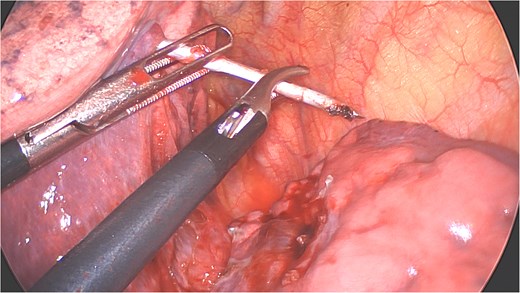

A clear minor pleural effusion and translucent scissural and para-aortic adhesions were visible. The adhesions of the pulmonary apex were released but no abnormality of the parietal pleura nor bone was visible. As the lung then collapsed, the pin became spontaneously visible protruding in the main fissure. As expected, the proximal part was in segment 2 and the distal half inside the apical segment of the lower lobe (S6) but it did not protrude outside of the parenchyma on either side (Fig. 4). The K-wire was easily removed by gently pushing back the parenchyma towards both extremities (Fig. 5). The pin seemed to be surrounded by a fine membrane that was coagulated at the visceral pleural entry point.

Distal part of K-wire stuck in segment 2 and the proximal part in the apical segment 6.

Extraction of the K-wire by pushing the parenchyma towards both extremities.

There was no spontaneous bleeding. For pneumostasis a single 3/0 PDS suture was placed on the visceral pleural exit site respectively the entry site of both lobes with subsequent negative air leak test. The chest was drained with a 24F drain through the lower trocar port wound (Fig. 6). After intercostal blocks with local anesthetics (Levobupivacaine 10 ml) the lung was insufflated under visual control. The total duration of procedure was 64 minutes and estimated total blood loss was <10 ml. The drain was removed on the first postoperative day (Fig. 2b) and the patient discharged on the second day. At 3-week follow-up he had no residual pulmonary symptoms, took no analgesic medication and had a normal X-ray. The broken proximal half of the wire was left in place. The patient gave his explicit consent for the publication of his case.